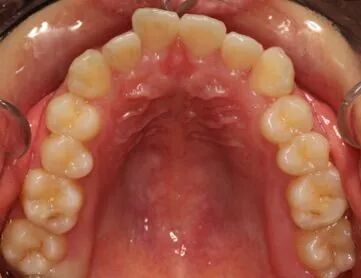

做过正畸的小伙伴们请来回答一个问题~ 矫治结束、摘下牙套之后 最怕的是什么?? 在这里,小编要分享一个正畸小伙伴的“血泪史” 大家引以为戒啊引以为戒!!! 经过3年的辛苦矫正,牙齿终于脱胎换骨~~一口整齐漂亮的小白牙,让我高兴了好一下下~~ 可是!但是!!可但是!!!刚拆了牙套才一年…牙齿就又回去了,又变得不整齐了… 呜呜~奶油冰激凌也弥补不了我的伤心~~我的小白牙为什么会这样?到底是为什么呢? 有图有真相 这是刚拆掉牙套时 这是摘牙套一年之后~~ OMG!!!为什么!! 我去找我的牙医~要去问问他! 医森认真的给我分析了原因.....恍然大悟! 01 牙周及牙龈纤维重建 牙齿经矫治移动后,被拉伸或压缩的牙龈及牙周膜纤维的张力尚未建立新的平衡,牙齿的位置不稳定,容易复发。尤其是牙槽嵴上纤维与横隔纤维的改建非常缓慢,所产生的张力容易使移动的牙再恢复原错位状态。此外,牙槽骨由过渡性骨改建正常牙槽骨也需要一定时间。 02 口周肌力的影响 治疗结束后,由于牙齿牙弓与颌骨的位置发生了改变肌动力平衡也因此有了变化,由于错牙合畸形形态学的改变往往先于功能和肌动力的改建,即原有的动力平衡对矫治后的牙齿、牙弓及颌骨位置会产生一定的负面影响医|学教|育网搜集整理,使之呈现不稳定状态。 03 咬合平衡未完全建立 在矫治过程中,由于改变了牙、牙弓和颌骨位置关系,因而破坏了原有已习惯的异常关系。新建的牙合关系还未达到颌面恰好吻合,与牙尖斜面的接触关系,还必须经过不断调整,在调整过程中,有复发的倾向。 04 不良习惯的影响 口腔不良习惯是造成错颌畸形的一个重要原因,若在正畸治疗结束时,仍未纠正口腔不良习惯,极容易导致错颌畸形的复发,比如异常吞咽、伸舌习惯导致开颌畸形复发 05 口腔正畸后需保持时间 戴用保持器的期限没有具体规定,一般应与错颌病因、错颌类型等因素有关。一般人认为保持时间为2年左右。保持时间越长,效果越稳定。 除了上述原因外,还可能与长智齿、不良习惯 ,不利的生长发育等有关…… 温馨提示 为提高居民口腔保健知识,增强口腔保健意识,为各单位团体、中小学校、社区组织提供免费口腔健康讲座、口腔健康义诊等公益服务。 如有需要请联系宣传科:18806332046 (费先生) 地址:望海路与正阳路交汇处(日照市中医医院东邻) 咨询热线:0633—2222226 关注下方二维码 了解更多内容经过医生的分析,我终于明白了原因……